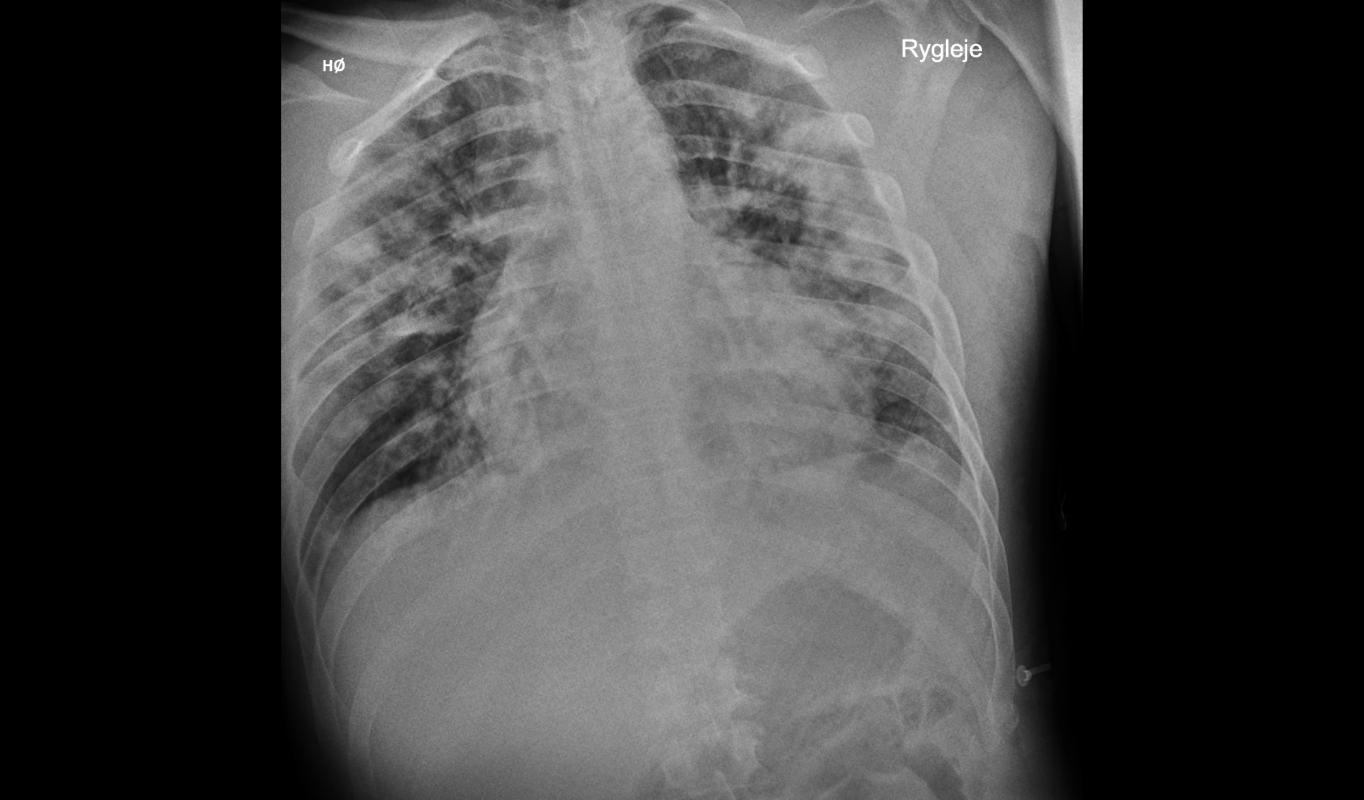

初次胸部 X 光检查显示双侧弥漫性肺泡浸润病变,提示肺炎。